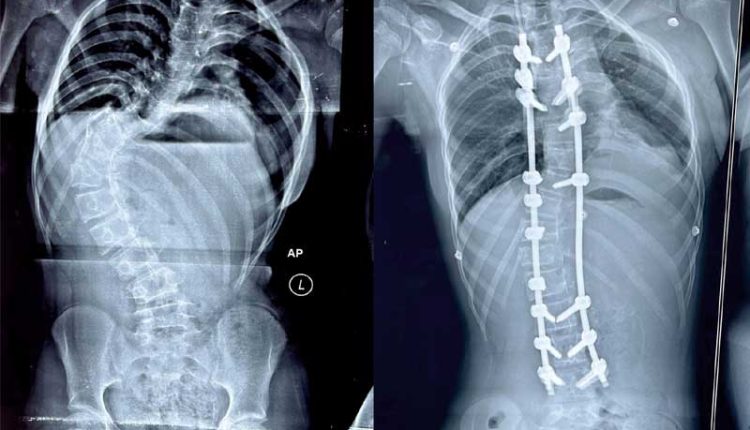

Bhubaneswar: Kalinga Institute of Medical Sciences (KIMS), Bhubaneswar has successfully given a new lease of life to a teenage girl from Bhadrak, who was battling a spinal deformity known as Scoliosis. The abnormal curve in her spine gave it an ‘S-shaped’ appearance, threatening her promising future. However, thanks to the expertise of the doctors at KIMS, her spine was meticulously corrected in a recent complex operation, and she is now on the path to a full recovery, ready to embrace a normal life once again.

Dr. Rout explained that the spinal deformity the girl suffered from is known as “idiopathic scoliosis,” a condition that typically develops between the ages of 10 and 15 and if left untreated, can lead to severe deformities and significantly impact self-confidence and self-esteem. Such patients often become targets of ridicule due to their appearance. Correcting the deformity at an early age is crucial, as it becomes more challenging to treat an advanced age.